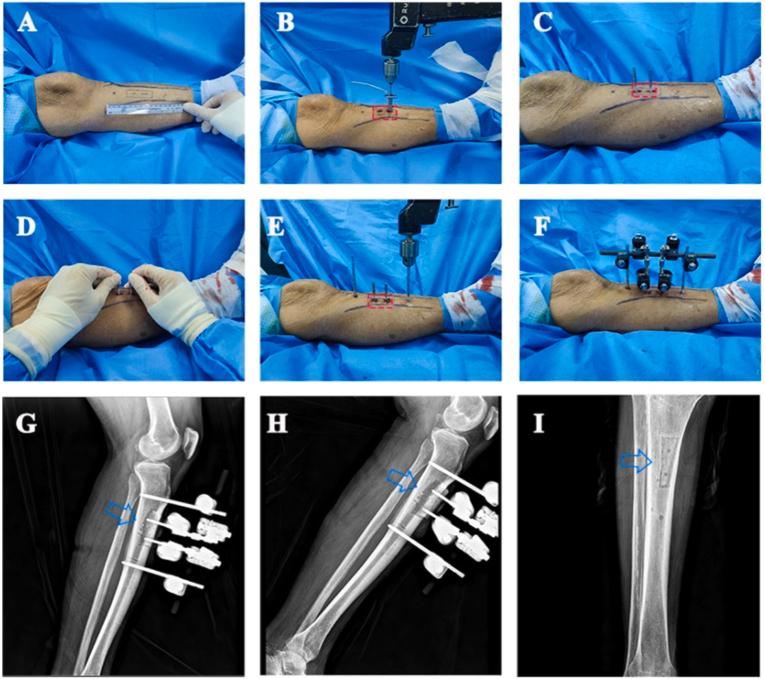

Tibial Cortex Transverse Transport (TTT) has been demonstrated to be an effective treatment for unilateral diabetic foot ulcers (UDFUs). However, this retrospective study was designed to compare the efficacy and safety of unilateral TTT on bilateral diabetic foot ulcers (BDFUs).

This retrospective study included a review of patients with TTT treated from January 2017 to August 2019, Propensity Score Matching (PSM) was performed to compare patients with BDFUs to those with UDFUs. Ulcer healing, recurrence, and major amputation rates were evaluated at 1-year follow-up. Changes in foot vessels were assessed in the BDFUs group using computed tomography angiography (CTA).

A total of 140 patients with DFUs (106 UDFUs and 34 BDFUs) were included in the study. UDFUs and BDFUs were matched in a 1:1 ratio (34 in each group) using PSM. No significant difference was observed at 1-year-follow-up [91.2% (31/34) vs. 76.5% (26/34), OR 0.315 (95% CI 0.08 to 1.31), P ​= ​0.10] and 6-month-follow-up [70.6% (24/34) vs. 50.0% (17/34), OR 0.85 (95% CI 0.15 to 1.13), P ​= ​0.08] in two groups. Significant differences in rates of major amputation and recurrence between the groups (P ​> ​0.05) were not observed. The BDFUs group appeared more angiogenesis of the foot by CTA after 8 weeks of operation.

Results of this study suggest that severe BDFUs can be effectively treated by unilateral TTT. TTT is easy to operate and effective, which may be a good alternative for treating severe BDFUs.